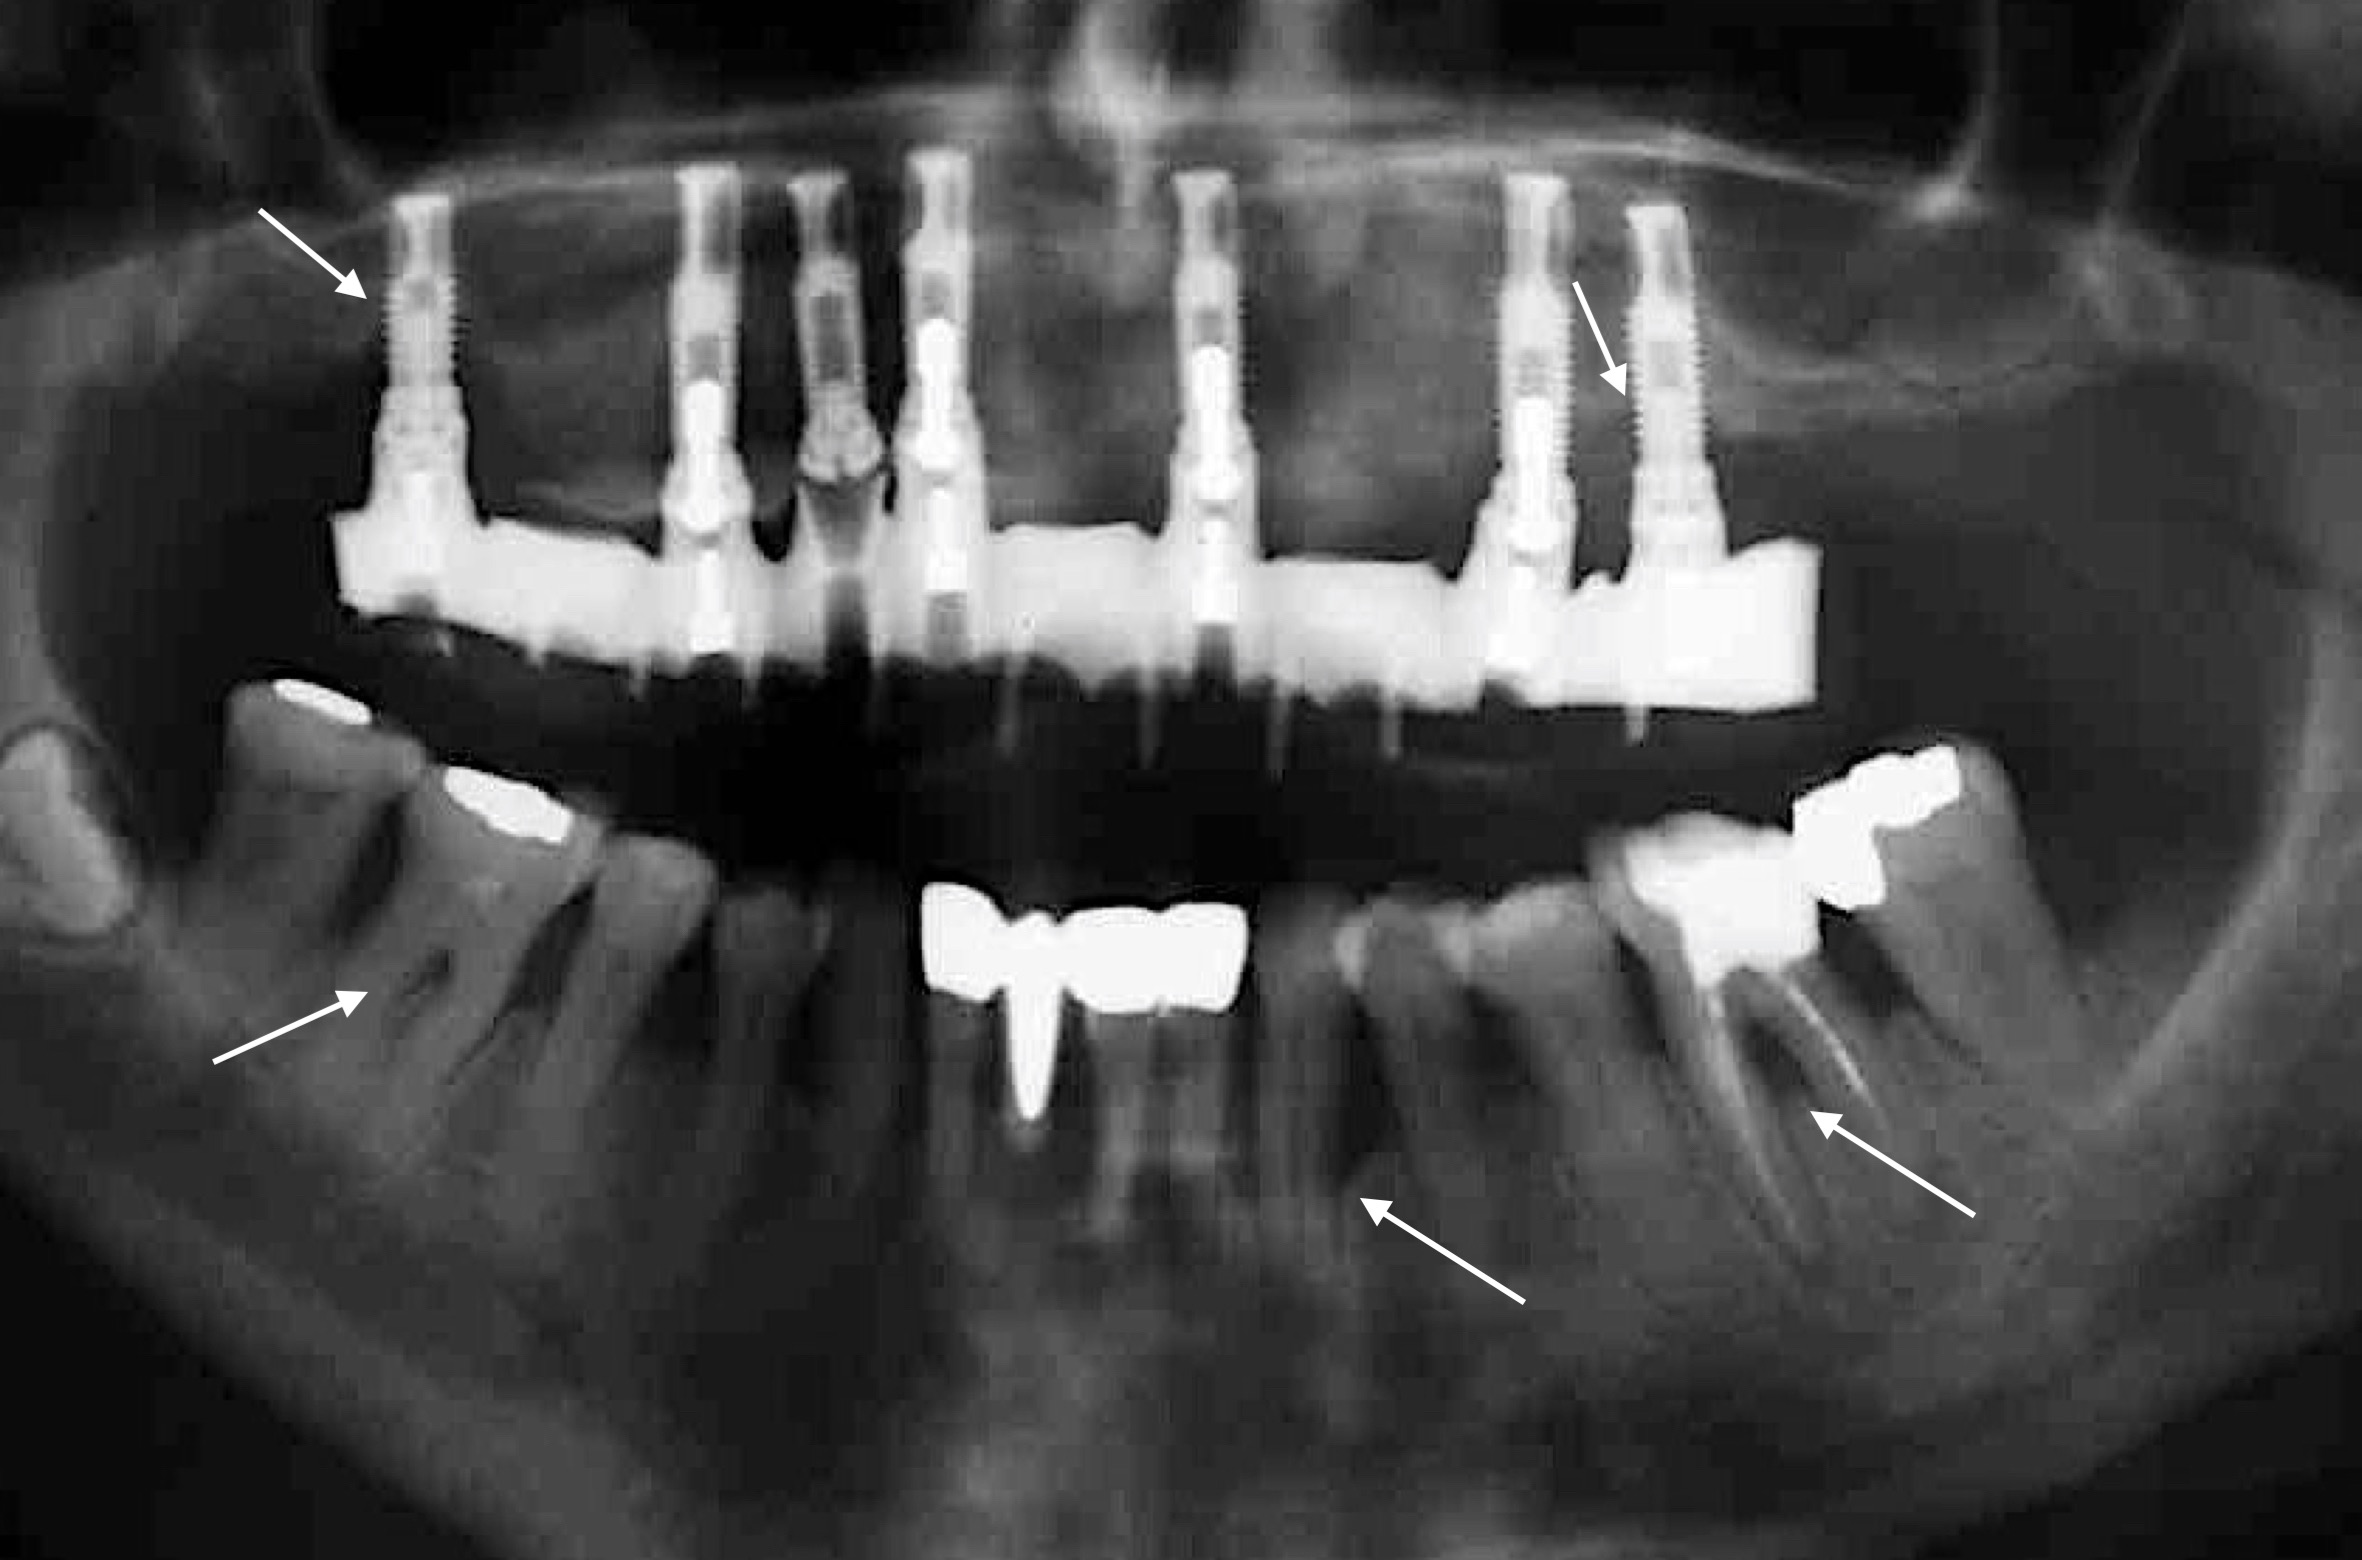

But just how great is the risk of periodontitis patients developing peri-implant mucositis or even peri-implantitis and, in the worst-case scenario, of experiencing implant failure compared with patients without periodontitis – smaller, the same or larger?

Numerous reviews from the last 10 years have shown that patients with underlying periodontal disease have a higher risk of implant failure (e.g. Renvert & Persson 2009, Sousa et al. 2016, and many others). In addition, this risk appears to be even higher among patients who have been diagnosed with generalized aggressive periodontitis (Monje et al. 2016). To avoid this complication wherever possible, the patient’s periodontal health must be maintained as strictly as possible. This means: 1) periodontal treatment must take place before implant treatment; 2) the patient’s oral hygiene must be rigorously optimized and, above all, the patient must be given precise new instructions after they have been fitted with their implant-retained prosthesis; 3) to prevent recurrence of the patient’s periodontitis and to enable early detection of peri-implant diseases, regular follow-up sessions must be scheduled and conducted; and 4) residual pocket probing depths should ideally be avoided after periodontal treatment! Why is the last point so important? A study from Australia (Cho-Yan Lee et al. 2012) showed very clearly that periodontitis patients with residual pocket probing depths (≥ 6 mm pocket probing depth) are at 4 to 5 times greater risk of developing peri-implantitis than periodontally healthy patients and periodontitis patients without residual pocket probing depths!